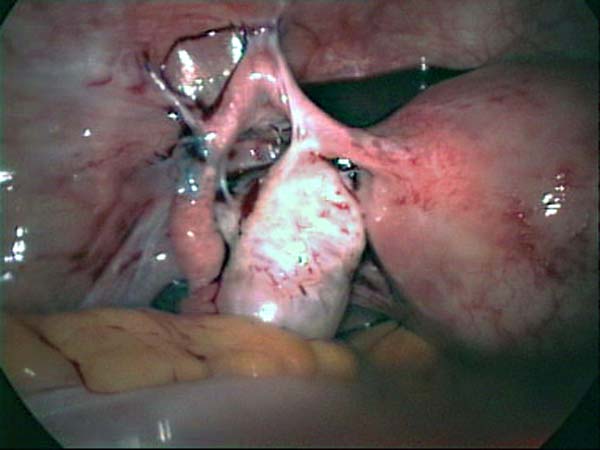

Photos laparoscopie Kyste ovarien Cystectomie ovarienne Septum utérin Grossesse tubaire